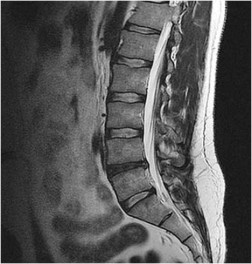

Question 13:

A 65-year-old male presents with neurogenic claudication. He reports pain radiating down both legs when walking, which is relieved by leaning forward on a shopping cart. MRI shows severe spinal stenosis at L4-L5. Which ligament thickens and contributes significantly to the dorsal compression of the thecal sac in this condition?

Correct Answer: Ligamentum flavum

Explanation:

In degenerative lumbar spinal stenosis, hypertrophy and buckling of the ligamentum flavum commonly cause dorsal compression of the thecal sac.